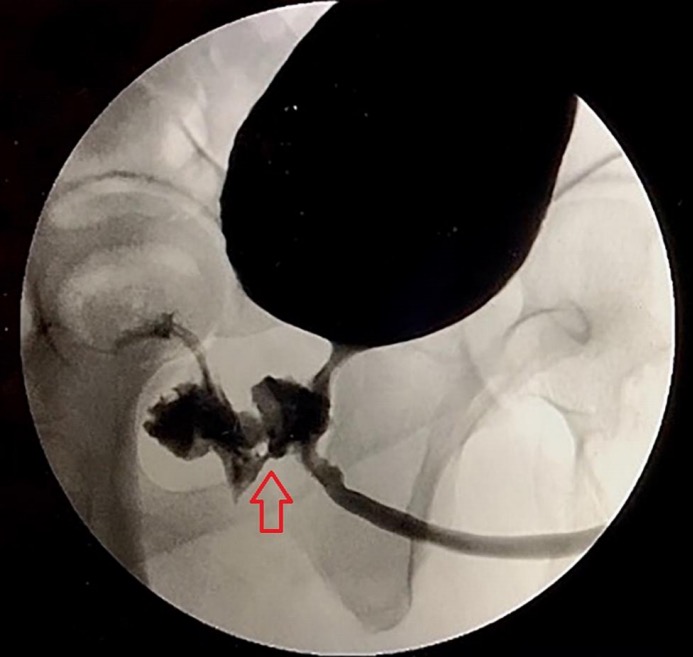

Após diversos exames, imagens revelaram a presença de uma fístula na região do reto e do aparelho urinário. O caso foi relatado por médicos no artigo "Um Curioso Caso de Ejaculação Anal". Ele foi tratado com antibióticos e submetido a uma pequena cirurgia para corrigir a região com a fístula.